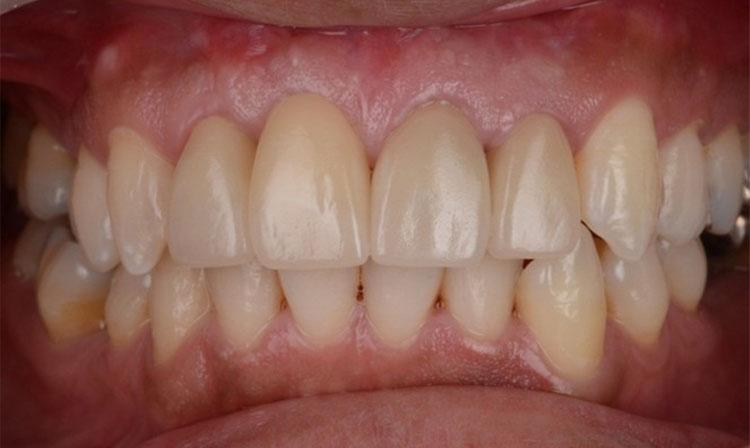

インプラント症例 Case2

Treatment cases

Before

After